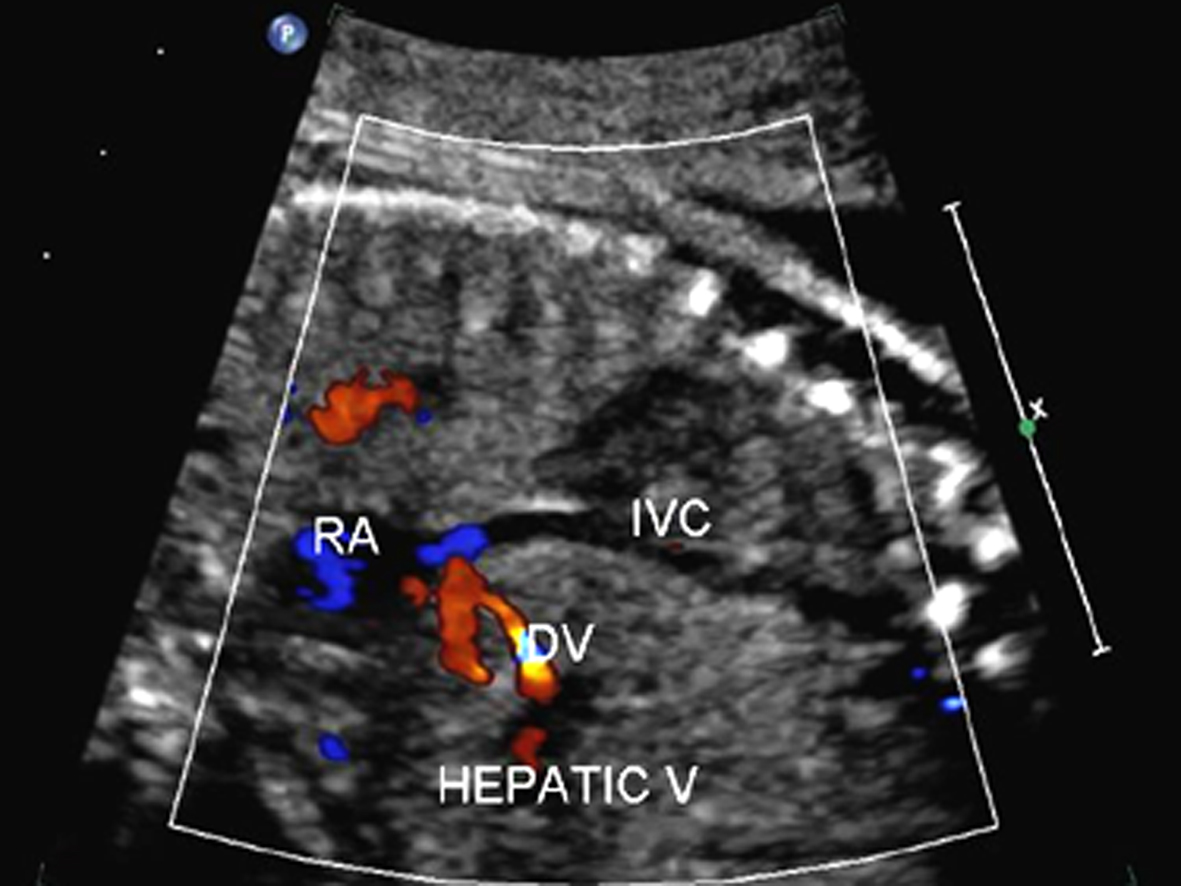

静脉导管(DV)位于门静脉与下腔静脉之间,连接脐静脉腹内段和下腔静脉,细小隐蔽,长4~6mm,直径0.7~1.5mm,在胎儿循环中发挥至关重要的作用。由于管腔狭细,长度较短,需要一定的技巧和经验方可显示。胎动、胎儿呼吸运动及胎位均可影响静脉导管的显示。胎儿安静状态下在胎儿正中矢状切面或胎儿中上腹横斜切面可以显示静脉导管内的血流。正常情况下脐静脉内径较大,静脉导管内径较细,由脐静脉延续的血流至此处流速增加,彩色多普勒血流显像常常显示快速血流镶嵌图形而容易辨认。检查静脉导管时应注意采取连续追踪扫查由脐静脉连续追踪扫查至下腔静脉,适当调节增益、脉冲重复频率并适当缩小取样区域,以准确显示静脉导管及其内部的血流(图4,5)。

图4 11周DV显示 B为A图(俯卧位)的示意图(暗图为未显示结构),C为胎儿仰卧位

图5 DV的彩色多普勒血流图 RA.右房;IVC.下腔静脉; HEPATIC V.肝静脉